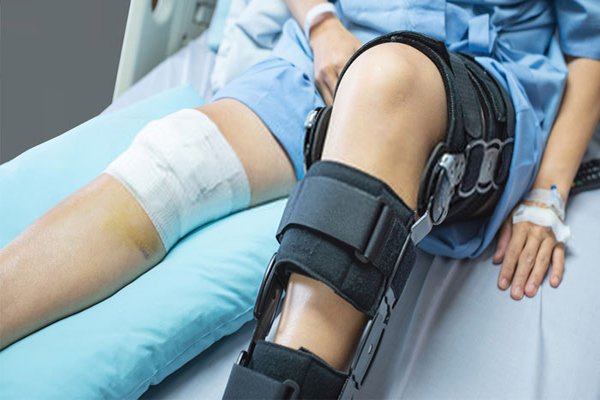

Joint Replacement (Robotic & Conventional):

◆ Total knee replacement

Fracture Care (Orthopedic Trauma):

◆ Expert management of orthopedic fractures, including complex traumatic and intra- articular fractures

◆ Fracture reduction and maintenance with plaster application avoiding surgery

◆ Surgical fracture fixation in absolutely indicated cases.